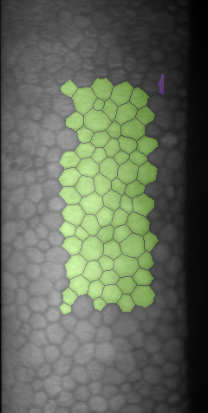

Specular microscopy assessment of the human corneal endothelium (CE) in Fuchs' dystrophy is challenging due to the presence of dark image regions called guttae. This paper proposes a UNet-based segmentation approach that requires minimal post-processing and achieves reliable CE morphometric assessment and guttae identification across all degrees of Fuchs' dystrophy. We cast the segmentation problem as a regression task of the cell and gutta signed distance maps instead of a pixel-level classification task as typically done with UNets. Compared to the conventional UNet classification approach, the distance-map regression approach converges faster in clinically relevant parameters. It also produces morphometric parameters that agree with the manually-segmented ground-truth data, namely the average cell density difference of -41.9 cells/mm2 (95% confidence interval (CI) [-306.2, 222.5]) and the average difference of mean cell area of 14.8 um2 (95% CI [-41.9, 71.5]). These results suggest a promising alternative for CE assessment.